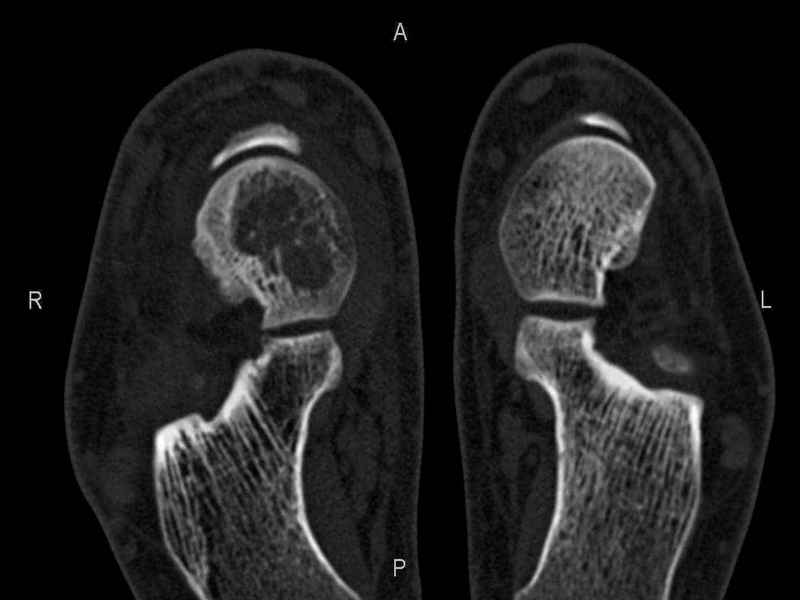

Рассекающий остеходрит + киста шейки тарана

Уважаемые коллеги, обратился за помощью пациент, мужчина, 25 лет. С жалобами на болевой синдром в области голеностопного сустава и среднем отделе стопы.

Травму отрицает. Со слов, болевой синдром в течении 1 года. Последние 1-1.5 мес периодически вынужден пользоваться костылями. После ограничения нагрузки боли уменьшаются. Соматически здоров. До появления болей активно занимался рукопашным боем.

На СКТ картина рассекающего остеохондрита блока таранной кости, киста шейки таранной кости с признаками импрессии суставной поверхности. А также - разрастания переднего края б\берцовой кости сопровождающиеся клиникой импиджмент синдрома.

Предполагаемый план лечения- удаление свободного фрагмента суставного хряща из трансмаллеолярного доступа с рассверливанием поверхности дефекта, кюретаж кисты шейки с заполнением полости биокомпозитом + дебридмент переднего отдела голеностопного сустава.